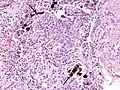

The abnormal chest x-ray and its interpretation remain the most important factors in establishing the presence of pulmonary fibrosis.[11] The findings usually appear as small, irregular parenchymal opacities, primarily in the lung bases. Using the ILO Classification system, "s", "t", and/or "u" opacities predominate. CT or high-resolution CT (HRCT) are more sensitive than plain radiography at detecting pulmonary fibrosis (as well as any underlying pleural changes). More than 50% of people affected with asbestosis develop plaques in the parietal pleura, the space between the chest wall and lungs. Once apparent, the radiographic findings in asbestosis may slowly progress or remain static, even in the absence of further asbestos exposure.[25] Rapid progression suggests an alternative diagnosis.

Asbestosis resembles many other diffuse interstitial lung diseases, including other pneumoconiosis. The differential diagnosis includes idiopathic pulmonary fibrosis (IPF), hypersensitivity pneumonitis, sarcoidosis, and others. The presence of pleural plaques may provide supportive evidence of causation by asbestos. Although lung biopsy is usually not necessary, the presence of asbestos bodies in association with pulmonary fibrosis establishes the diagnosis.[26] Conversely, interstitial pulmonary fibrosis in the absence of asbestos bodies is most likely not asbestosis.[11] Asbestos bodies in the absence of fibrosis indicate exposure, not disease.

The arrow points to an uncoated segment of asbestos fiber in this ferruginous body.

The black arrows point to ferrugionous bodies that are located at the periphery of a focus of non-small cell lung carcinoma, NOS.